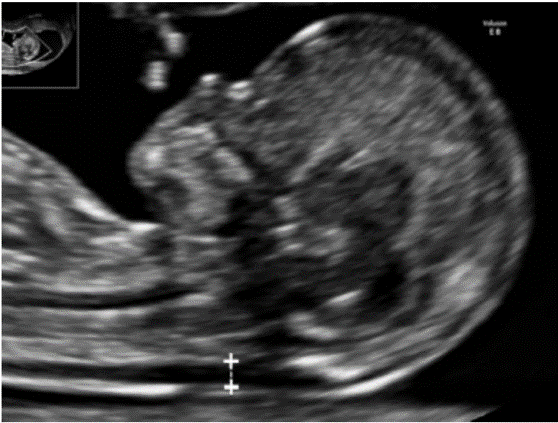

* Bilateral ventricular dilatation:

Patient N.T.T - 25 years old - History of 1 miscarriage - Natural pregnancy

![]() |

| Figure 7. Bilateral ventricular dilatation (diameter greater than 10mm) |